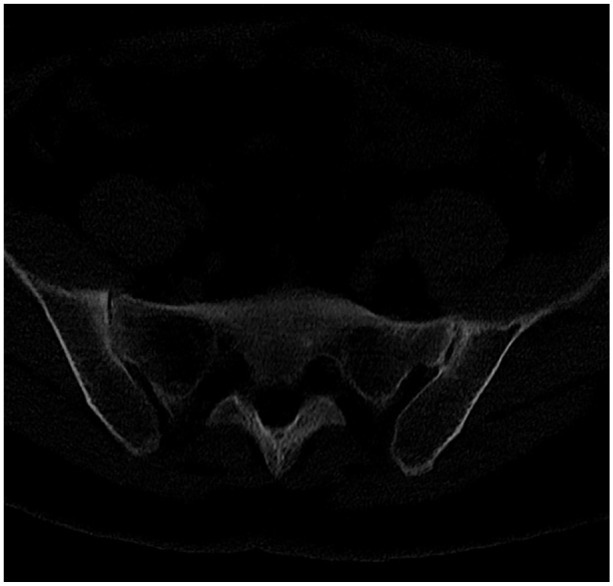

Abstract Image